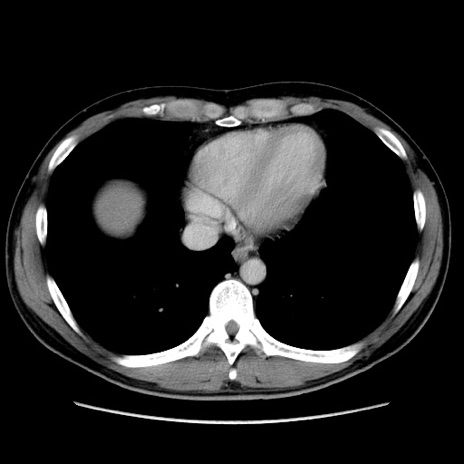

症例36(横断像)

【症例】20歳代 男性

【主訴】心窩部痛

【現病歴】今朝より上腹部痛あり。一旦軽快していたが再度出現したため救急要請。昨日夕に白身の魚を含む刺身を食べた。

【身体所見】BP 136/89mmHg、HR 74/min、BT 37.0℃、腹部:膨満、軟、心窩部に圧痛あり。反跳痛なし、筋性防御なし、腸雑音やや亢進あり。

【データ】WBC 17700、CRP 0.48